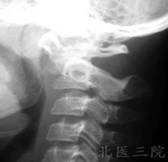

寰樞關節脫位除外上頸椎的其他部位損傷,必須藉助X線攝片X線張口位攝片,主要特徵表現是樞椎齒狀突與寰椎兩枚側塊間距不對稱。但張口拍片時合作不好可使投影位置偏斜,引起兩者間隙異常,或不能滿意顯示該區解剖結構。必要時多拍幾次片,排除因投影位置不當造成誤診,側位X線片能清醒顯示齒狀突和寰樞椎弓之間的距離變化。正常情況下在3mm以內,必要時CT掃描,與寰椎椎弓骨折及上頸椎畸形鑑別。應注意嚴重的陳舊性半脫位,表現為斜頸及運動受限,頸部活動時疼痛。可導致面部發育不對稱斜,頸的出現可引起對側胸鎖乳突肌痙攣。

(1)寰齒間距增大:側位片可見寰椎前弓後緣與齒狀突相對應點的距離,正常成人和兒童分別為3mm和4mm,如成人寰齒距為3mm-5mm之間,常提示有橫韌帶撕裂。如寰齒距為5mm-10mm則提示橫韌帶有斷裂,並部分輔助韌帶撕裂,如10mm-12mm則證明全部韌帶斷裂。

(2)枕頸伸屈功力性側位片:顯示屈位時寰椎前弓和齒狀突呈“V”型間隙,提示橫韌帶下纖維以外的部分撕裂,使寰樞椎藉助未斷纖維束起支點作用,而顯示寰齒間隙上部分分離呈V型。

(3)枕頸伸屈動力性側位片,顯示寰椎前後不穩徵象,確診為韌帶損傷。